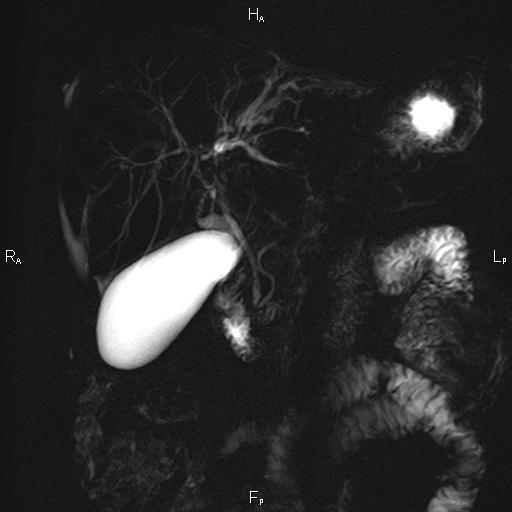

Ανώδυνος ίκτερος και παθολογικά ηπατικά ένζυμα. Ιστορικό πιθανής σκληρυντικής χολαγγειίτιδας

Μαγνητική τομογραφία.

Οι αρχικές εξετάσεις εκλογής, όσον αφορά τον απεικονιστικό κυρίως έλεγχο, σε ασθενή προσερχόμενο στο Νοσοκομείο με αποφρακτικό ίκτερο, είναι το υπερηχογράφημα και η αξονική τομογραφία. Οι εξετάσεις αυτές έχουν αποδειχθεί ικανές να προσδώσουν έμμεσα και άμεσα στοιχεία για τη διάγνωση του χολαγγειοκαρκινώματος, όμως κυρίαρχη εξέταση για την διάγνωση του χολαγγειοκαρκινώματος είναι η μαγνητική τομογραφία (MRI, MRCP, MRA).